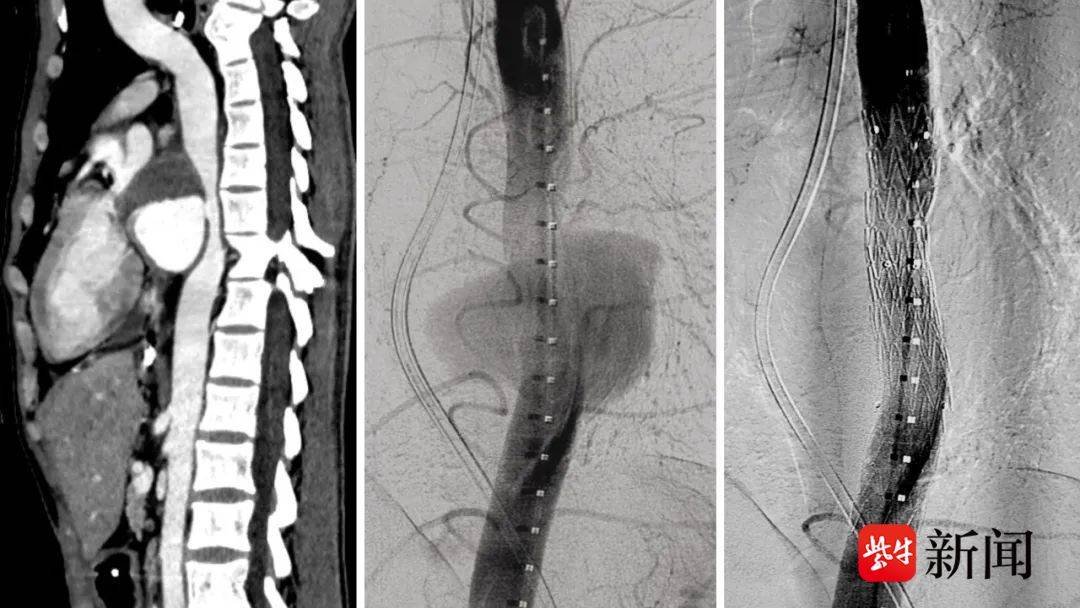

患者术前CT(左)、术中(中)及术后(右)DSA造影

36岁小伙张良(化名)既往因克罗恩病经历了多次手术,在医院肠瘘外科康复期间出现胸闷不适,行增强CT检查发现了巨大的“胸主动脉假性动脉瘤”,破口位于主动脉前壁,最大直径达8cm,这无疑使得患者本就危重的病情雪上加霜。由于瘤体巨大,已经对心脏、食管及气管造成了压迫症状,必须尽快进行手术修复,否则一旦破裂,风险极高。

考虑到患者营养状态较差,且因慢性炎症导致结缔组织及血管条件不良,科室详细讨论后决定以微创的胸主动脉腔内修复术为优先方案,同时也做好开胸手术的准备。术前,胸外科刘长建主任对患者CT进行精密测量,最终在麻醉科、介入科的配合下精确植入支架,完美隔绝了瘤腔血流并“拆弹成功”!术后,患者转回肠瘘外科,由范朝刚主任团队予以专业的肠内营养支持治疗。